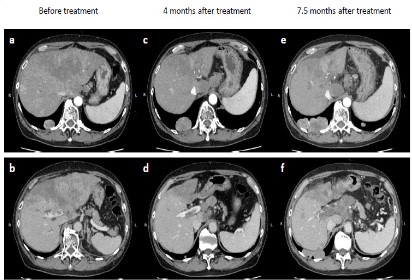

After 4 months and six cycles of combination therapy, abdominal CT was conducted with the tumor assessment. Contrast-enhanced CT revealed size reduction of the primary liver tumor (Figure 1c). However, progression of PVTT was observed (Figure 1d). Despite lack of apparent ascites, lung metastases were increased in size (Figure 2b). In addition, serum DCP and AFP levels had also increased. According to the modified Response Evaluation Criteria in Solid Tumors (mRECIST) [8], the tumor response was considered to be Progressive Disease (PD).

The patient started to take lenvatinib for 12 mg per day. After administration of lenvatinib, his liver function was maintained, indicated by CP-A liver function (score 6). At 3.5 month after initiation of lenvatinib, repeat CT assessment showed no significant increase in the size of hepatic tumors (Figure 1e), corresponding to Stable Disease (SD) by mRECIST. However, further progression of PVTT was observed (Figure 1f). At the same time, left hemiplegia suddenly occurred, and brain magnetic resonance imaging (MRI) indicated a metastatic tumor (Figure 2c). Therefore, lenvatinib administration was immediately stopped, and radiation therapy was initiated for brain metastasis. After the patient recovered from this brain metastasis, ruptured esophageal varices caused acute bleeding. Following emergency endoscopic treatment, his liver function and general condition deteriorated, and he died at 8.5 months after initiation of treatment. Clinical course is summarized in Figure 3.

Figure 1: Changes in hepatic tumor after atezolizumab plus bevacizumab and subsequent lenvatinib. Representative images at different times after systemic therapy. Contrast-enhanced computed tomography (CT) revealing a diffuse type hepatocellular carcinoma located primarily in segment 4 before treatment (a). The portal vein tumor thrombus has spread from the main portal trunk to the right portal trunk (b). Abdominal CT at 4 months after treatment showing reduction in the size of the primary tumor (c), but progression of portal vein tumor thrombus is also observed (d). The tip of the portal vein tumor thrombus has invaded into the bifurcation of the anterior and posterior branches; the anterior branch is filled with the tumor thrombus. Abdominal CT at 7.5 months after treatment indicating stable status of the primary tumor (e). The portal vein tumor thrombus has further increased in size, and the main portal trunk is fully occluded (f). The tumor thrombus has spread from the bifurcation of the anterior and posterior branches to the peripheral branch without patency.

a, c, e; arterial phase of enhancement. b, d, f; portal phase of enhancement.